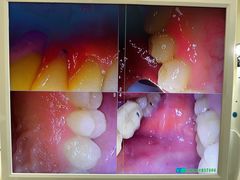

• 佛山中大口腔医院·市二级口腔专科医院

• -佛山中大口腔医院·市二级口腔专科医院